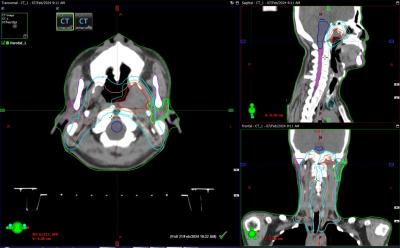

Perencanaan Penyinaran (Planning)